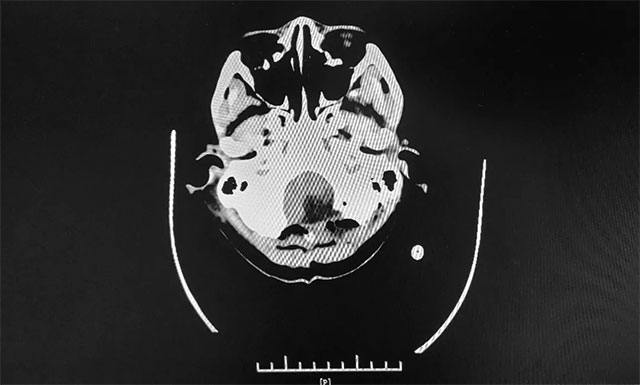

▲ 術(shù)前MR影像:左側(cè)小腦半球及小腦蚓部占位

▲ 術(shù)后CT顯示腫瘤被切除